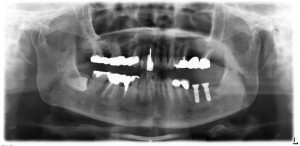

左下の大臼歯の成熟側へ2本のストローマンBLインプラントRC41.Φ10mm×2本を埋入しました。

手前の第2小臼歯は外側へ倒れて生えていますので、インプラントは正しい位置に入っています。

オペ後のレントゲンです。